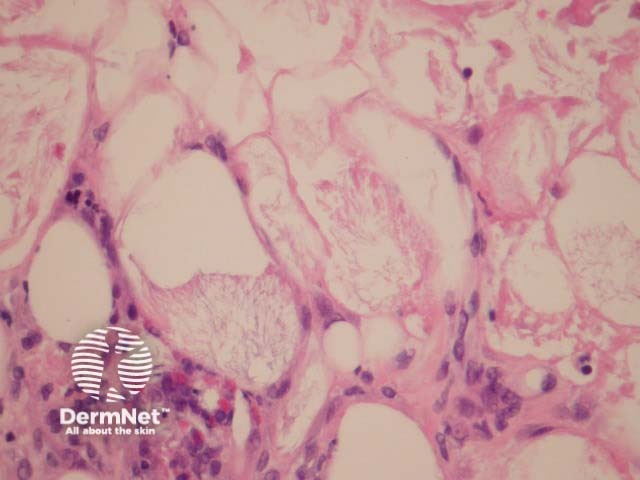

Poststeroid panniculitis presents as lobular panniculitis with a mixed inflammatory infiltrates without vasculitis. Needle-shaped crystals within adipocytes are characteristic (figure 1). The clefts may be surrounded by foreign body giant cells.

Figure 1